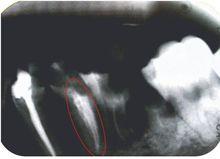

效果對比

側方加壓效果VS熱牙膠充填

熱牙膠充填